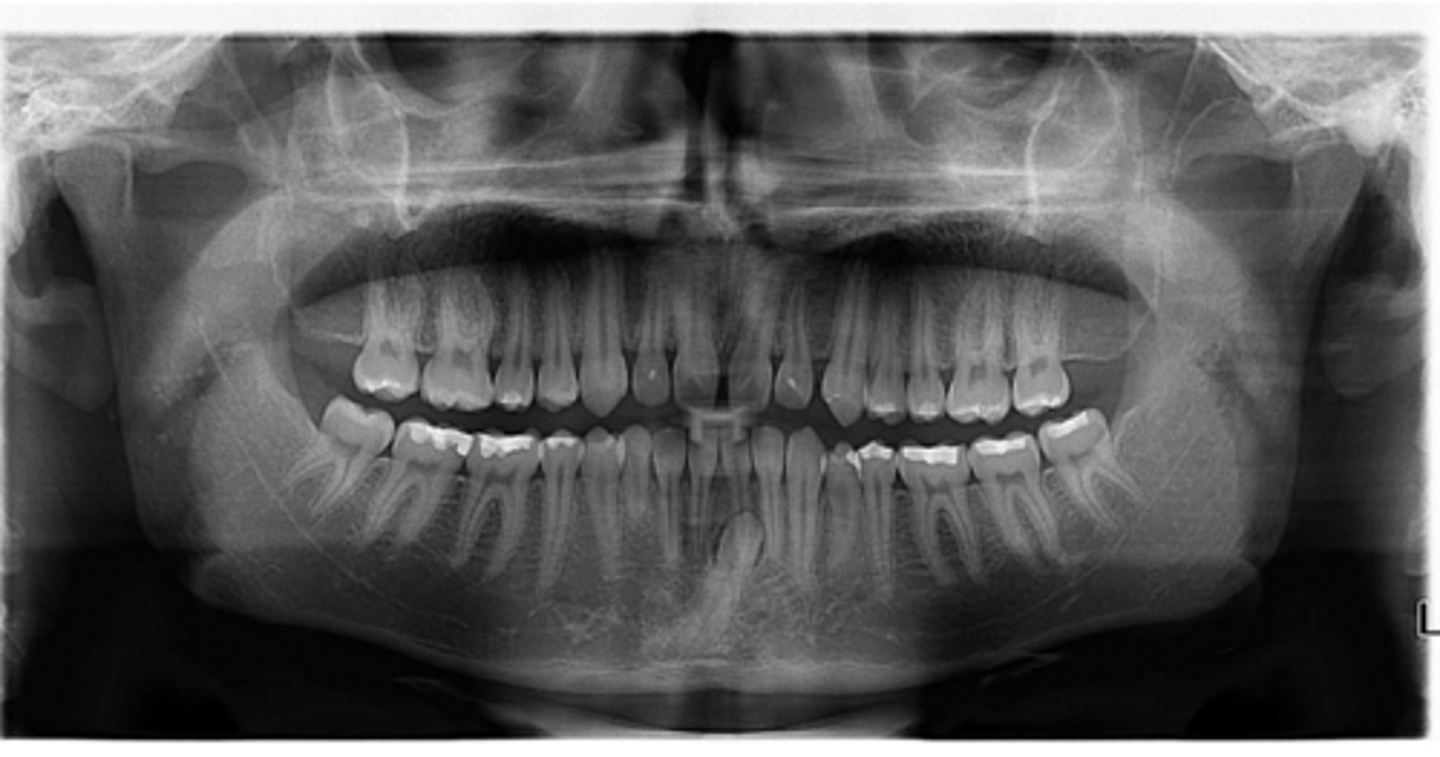

Premolar #13 (unerupted in pano) is more tilted than the opposing side (#4), which indicates an ectopic eruption pattern.

(Primary teeth w/o resorbing roots is also present)

What abnormalities/concerns do you see in this pano?

Third molars and mandibular right second premolar

Are there any congenitally missing teeth in the maxillary arch?

#29 (mandibular right second premolar)

Are there any congenitally missing teeth in the mandibular arch?

mandibular right second molar

Are there any retained primary teeth?

maxillary canines

Are there any impacted teeth?

Yes

Is there crowding?

More or less

Are the condyles symmetrical?

Maybe?

Is there any pathology?

Are there any ankylosed primary teeth?

No, just one in an odd position

Is there any ectopic eruption?

No

Are there supernumerary teeth?